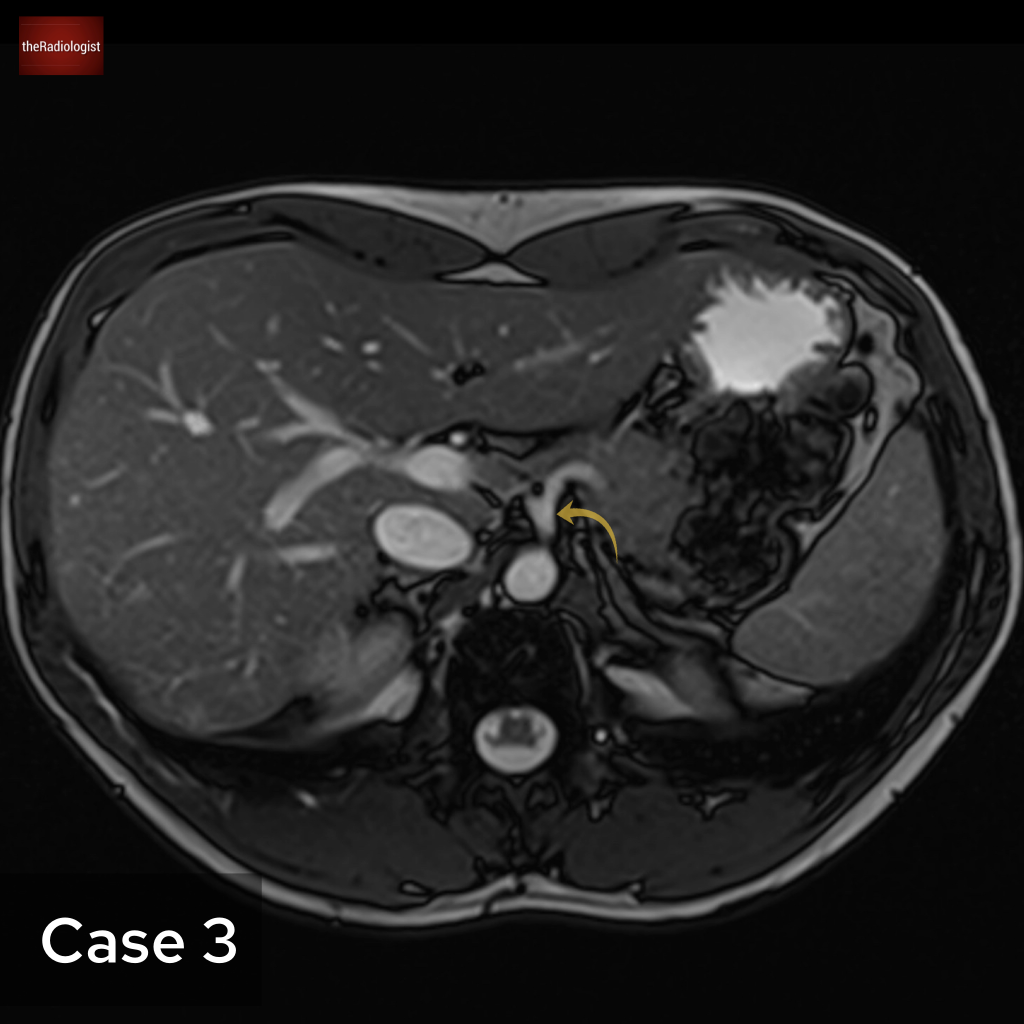

Case 3

Now let’s look at an abdominal MRI. What is the arrow pointing at?

Choose from one of the following: